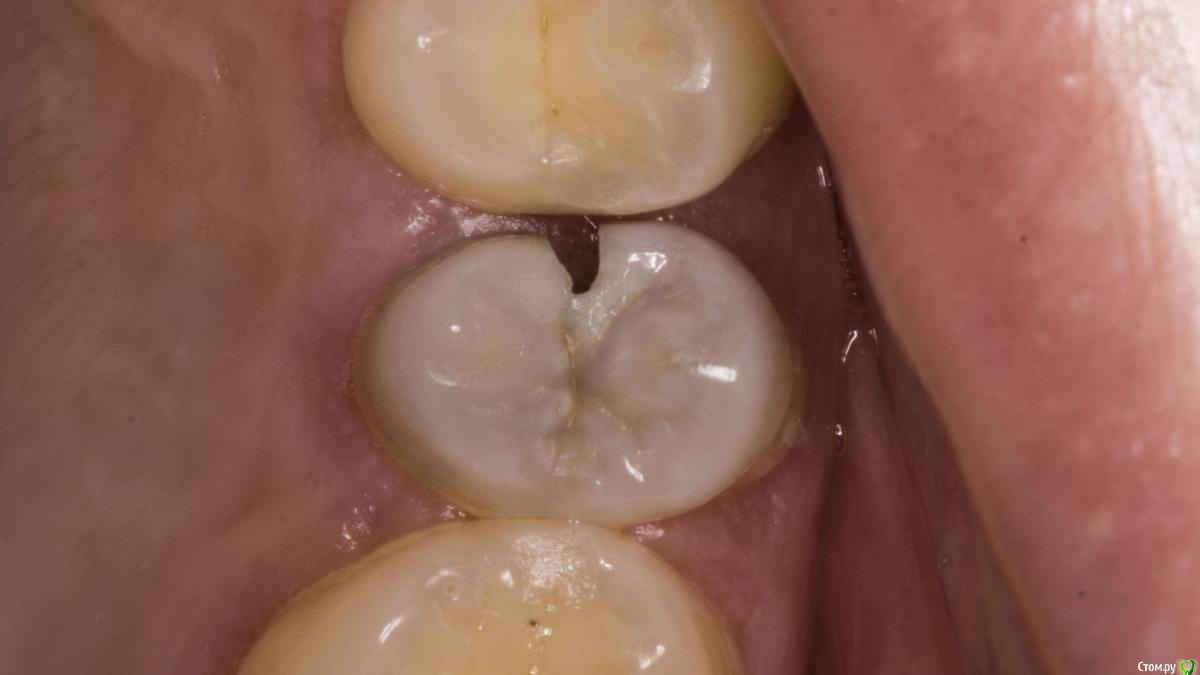

Kolchanov Опубликовано 19 апреля, 2018 Поделиться Опубликовано 19 апреля, 2018 Каплан, а есть какой-нибудь кейс с реальным поддесневиком. Где матрицу по полчаса вкорячиваешь. А то я все понимаю, эргономика, туда-сюда, но меня не покидает ощущение, что, когда попадается реально сложный случай, то микроскоп со вздохом отодвигается и начинается реальная жизнь стоматолога 7 Ссылка на комментарий

Kolchanov Опубликовано 19 апреля, 2018 Поделиться Опубликовано 19 апреля, 2018 Тут на фейсбуке какой-то доктор, кажется из лекторов, показывает случай с "поддесневым" разрушением, как он его назвал. И говорит, что чтобы не изменять профиль матрицы надо тефлоном подоткнуть вместо клина. А я смотрю и глаза протираю. Не вижу поддесневика. Коффер инвертирован, все путем. Ну, надо видеть конечно. Но я к чему, неужели только у меня что ни день то кариес-поддесневик? Ссылка на комментарий

Паращук Роман Опубликовано 20 апреля, 2018 Поделиться Опубликовано 20 апреля, 2018 Поддесневиков каждая третья полость. Далее или удлиняем и с помощью молотка и чей-то матери тулим матрицу,или удаляем. Ссылка на комментарий

Л Ю С Я Опубликовано 20 апреля, 2018 Поделиться Опубликовано 20 апреля, 2018 Матрицу тоже можно глубоко засунуть, не проблема, поджать фумкой, клином. Но контакта плотного получить, вот это реальная проблема 1 Ссылка на комментарий